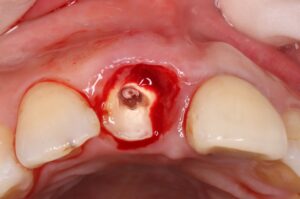

3、右の前歯が矯正的挺出が終了した状態。歯を引っ張りあげることで歯肉も一緒に上がってくる。(図3の状態)

4、歯周外科処置を行って歯肉を切除して下げた状態。(図4の状態)